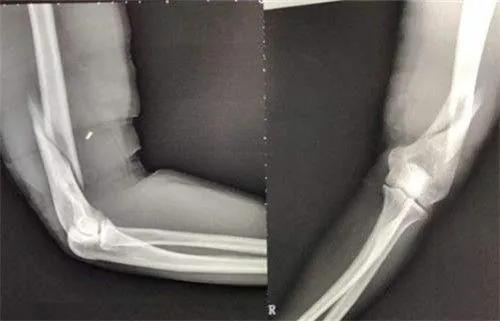

许多人在赛前不做任何准备活动,更有求胜心切者,为了战胜对方,突然“先发制人”,“不宣而战”,“出其不意”地将对方腕部猛然扳倒,败者不甘示弱,竭尽全力奋起翻腕,比赛达到高潮,危机也随之而至。只听“咔嚓”一声,参赛者一方的手臂突然无力地倒下,动弹不得,原来,肱骨骨折了。

而两种相逆向的扭转力,刚好在肱骨内旋肌附着点之下相交,容易在相当于肱骨干的中下段部位发生螺旋型骨折。扳手劲时,作用于肘部急剧的牵拉力,在尚不足以引起韧带和关节囊损伤之前,可能已超过骨骺板所能耐受的程度,从而发生肱骨上髁撕脱性骨折。

是不是成人扳手腕就不会有什么危险呢?不对。当双方用力扳腕时,两个相反方向的逆转力互相作用,其扭转力交合于上臂内旋肌与肘关节之间的肱骨干中下部时,方一方即将被扳倒而用力企图翻腕时,肌力要超过对方几倍才能成功,但这时因肘关节已被对方固定住,只能靠上臂内旋转肌强力收缩,超过负荷,就可能使肱骨中下段发生螺旋形骨折。这种情况一般发生在18岁以上的人,也就是肱骨内上髁完全与肱骨体封合以后。